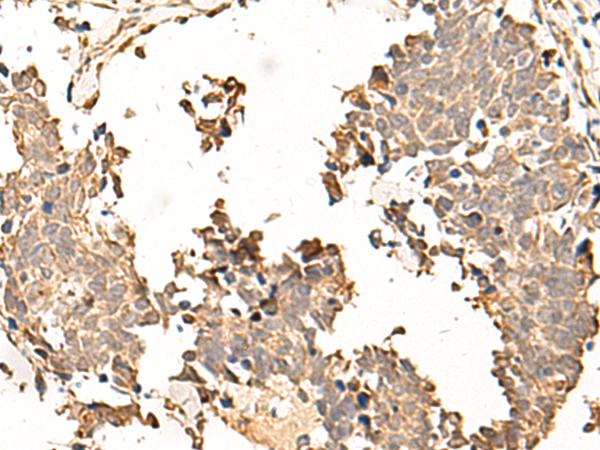

分类: 科研抗体货号: P05544别名: IRP; INT1L1应用: WB,IHC反应种属: Human, Mouse